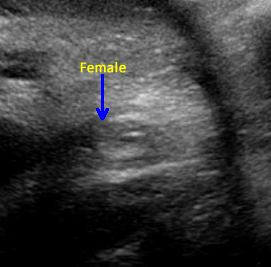

Above. Ovarian cyst. Case 1. 35 weeks gestation. Fetal gender is ascertained and confirmed to be female.